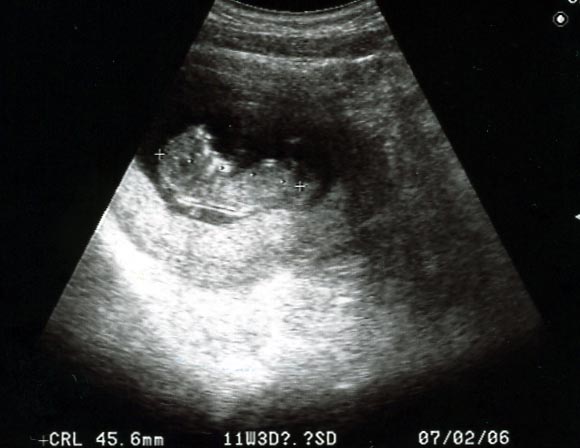

本日のこっこちゃん↓

10w6d

いきなり人間っぽく進化しました。

そして今日から経腹エコーでした。

先生がぐりぐりしている間手足じたばたしてました。

うう…白黒だけど可愛いよ…。

旦那にも見せたい…じたばた…。